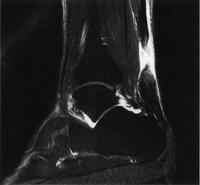

作業療法士実地問題 -

多発性硬化症患者の頭部MRIを別に示す。矢印で示す病変部位と症状との組合せで正しいのはどれか。

1

① — 左運動失調

2

② — Lhermitte徴候

3

③ — 右聴覚障害

4

④ — 視野障害

5

⑤ — 運動性失語